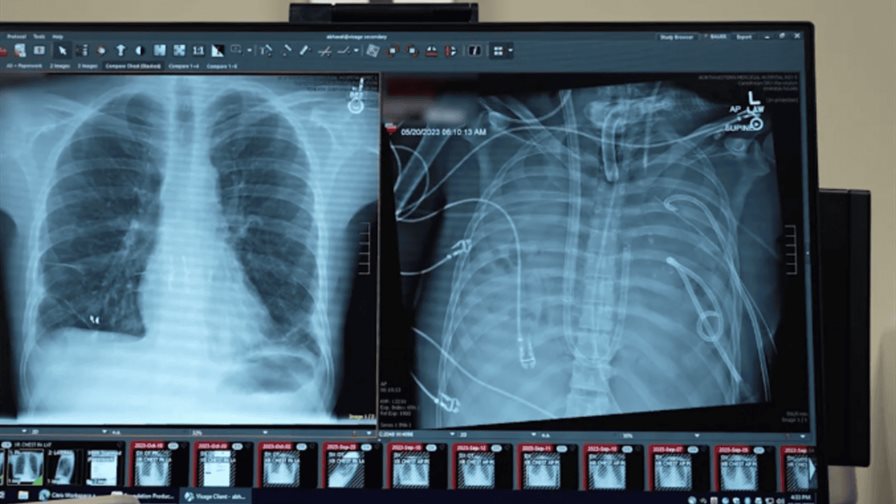

Un equipo de científicos ha conseguido que un paciente con una grave afección pulmonar sobreviva gracias a un sistema pulmonar extracorpóreo que le mantuvo vivo hasta que se le pudo realizar un doble trasplante de pulmón, una estrategia que podría emplearse como "puente salvavidas" hasta la intervención, según un estudio.

El paciente, un hombre de 33 años, había desarrollado síndrome de dificultad respiratoria aguda (SDRA), una afección potencialmente mortal en la que la inflamación y la infección sobrepasa a los pulmones.

El síndrome, que se desencadenó con una gripe y empeoró con una neumonía bacteriana, hizo que el paciente tuviera una infección tan grave que sus pulmones quedaron dañados de forma irreversible. Con el tiempo, su corazón y sus riñones también comenzaron a fallar.

Para ello, el equipo diseñó un sistema extracorpóreo de pulmón artificial que sustituyó temporalmente las funciones pulmonares. El sistema oxigenaba la sangre, eliminaba el dióxido de carbono y ayudaba a mantener un flujo sanguíneo estable a través del corazón y el cuerpo.

Cuando se retiraron los pulmones infectados, la condición del paciente mejoró, su presión arterial se estabilizó, la función de los órganos se recuperó y la infección remitió.